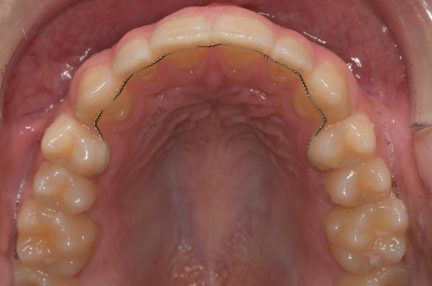

- L'hyperexpansion de la première prémolaire supérieure droite a été corrigée en planifiant le mouvement lingual avec contrôle simultané du couple.

État final